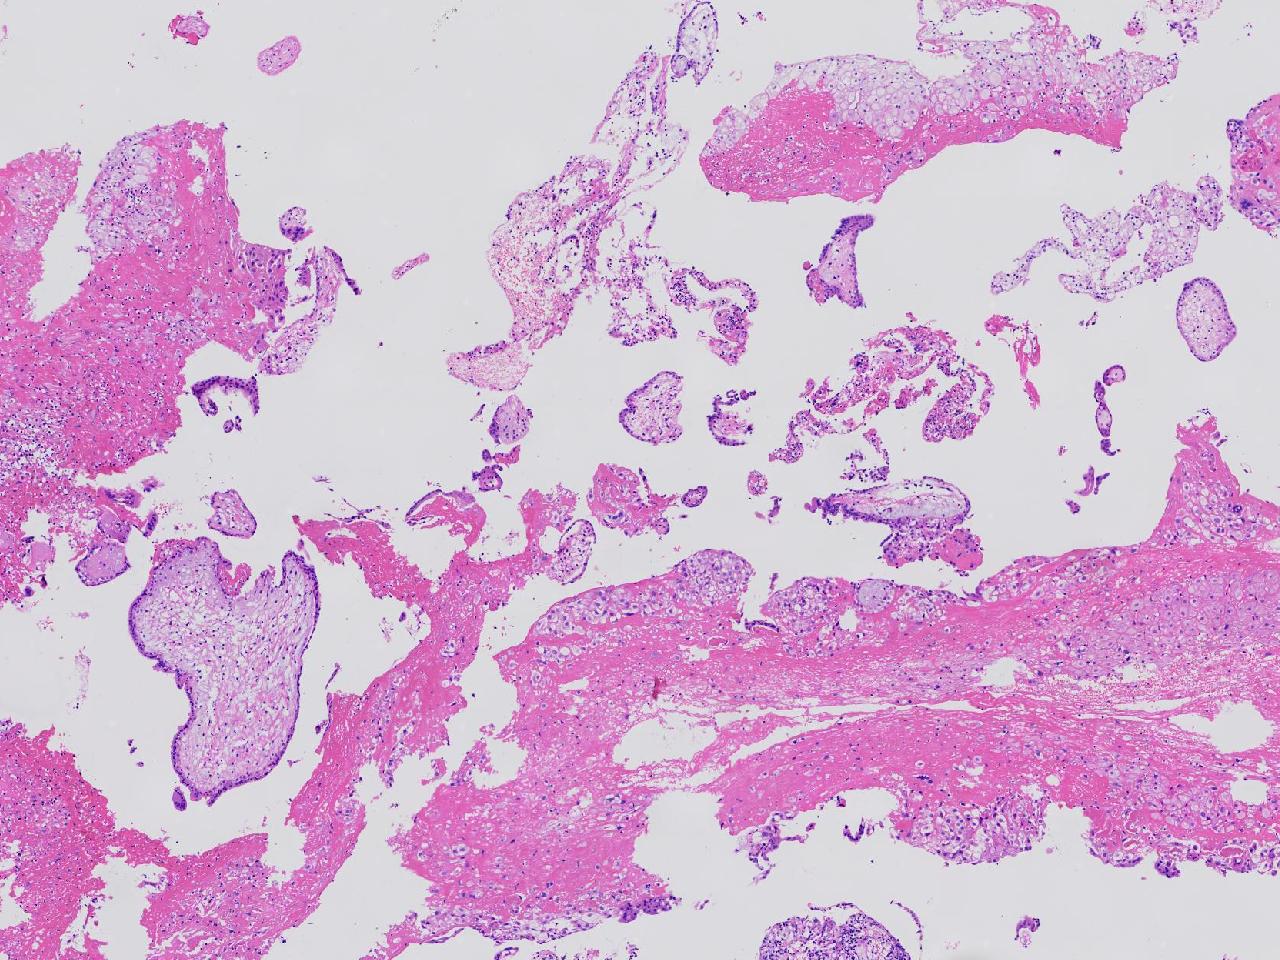

女,29岁,药物流产20余天,阴道少量出血20余天。行诊刮术。

宫腔内容物

灰粉色不整形软组织多块,4X3X3厘米,部分为血凝块。

送检组织为胎盘绒毛及蜕膜组织及滋养层细胞考虑为不全流产